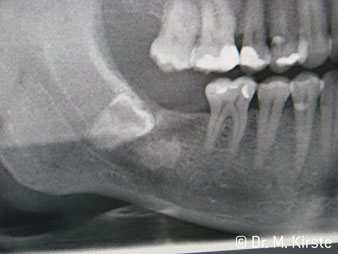

45° ъгъл на наконечника е специално избран поради неговата широка гама от предимства. Колеги, които работят хирургия, и за които този наконечник е главно създаден, скоро ще оценят възможността за ефективна работа в силно ограничени пространства. При екстрахиране на мъдреци, в частност (фиг. 2), няма нужда от голямо разширяване на меката тъкан в областта на бузата (фиг. 3). Дизайнът на главата на наконечника, в съчетание с лекото завъртане на главата по време на препарация, позволява бърза и безопасна работа в ретромоларната област.